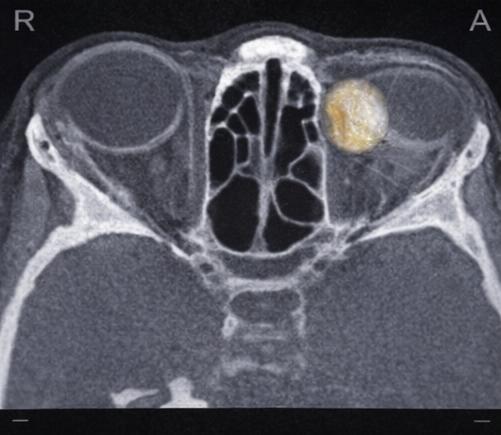

A computed tomography (CT) scan of the orbits revealed a well-circumscribed, hypodense lesion located in the superotemporal extraconal space of the right orbit. The lesion demonstrated fat attenuation and caused mild pressure remodeling of the adjacent frontal bone without cortical breach or erosion. There was no enhancement after contrast administration and no evidence of intracranial extension.

These imaging features were highly suggestive of a superficial orbital dermoid cyst. Magnetic resonance imaging (MRI) was deemed unnecessary due to the absence of deep orbital involvement or neurological signs.